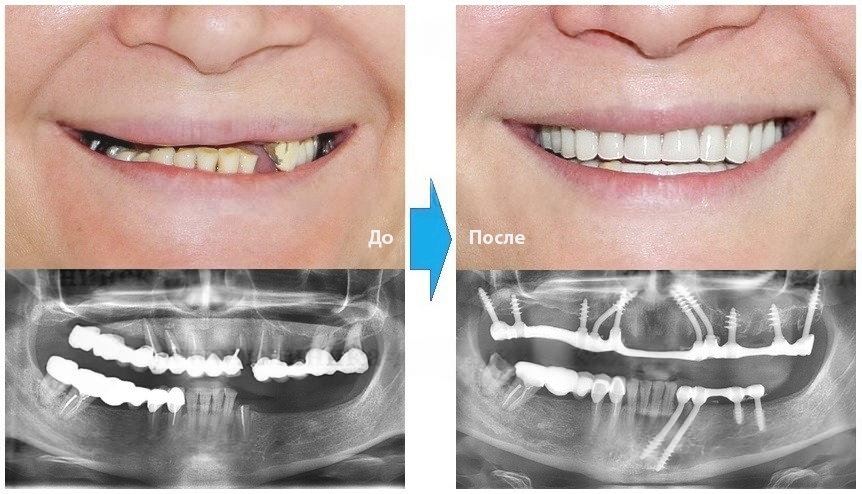

Базальная имплантация — это инновационный метод восстановления зубного ряда, при котором импланты фиксируются в глубоких слоях костной ткани, включая базальный слой. Этот способ особенно эффективен для пациентов с недостатком костной ткани, поскольку позволяет обойтись без сложных процедур костной пластики и синус-лифтинга.

При традиционной имплантации пациентам с атрофией костной ткани требуется дополнительная костная пластика, что увеличивает сроки и стоимость лечения. Базальные импланты фиксируются в глубоких слоях кости, которые не подвержены атрофии, что позволяет избежать лишних процедур.

Благодаря особой конструкции базальные импланты сразу же обеспечивают прочную фиксацию. Это позволяет пациенту практически сразу после операции вести привычный образ жизни, не опасаясь расшатывания конструкции.